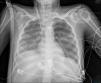

Mujer de 19 años, con antecedente de miopatía de Steinert, intubada por distrés respiratorio grave tras laparotomía exploradora por seudooclusión intestinal. En aspirado traqueal, E.coli sin mecanismos de resistencia. Muy mala mecánica pulmonar (compliance inferior a 2ml/cmH2O) y sin respuesta a maniobra de prono, se canula ECMO veno-venoso y, ante las altas presiones en la vía aérea con 4ml/kg de peso ideal, se cambia ventilación por ventilación con liberación de presión en la vía aérea (APRV): presión alta 15cmH2O; tiempo alto 6s; tiempo bajo 0,3s. Inicialmente 10ml de volumen espirado. La evolución radiográfica se muestra en las imágenes (fig. 1: día0; fig. 2: día2; fig. 3: día5). Este caso es un ejemplo de cómo la ventilación por APRV mientras aseguramos el intercambio gaseoso con el ECMO puede ser útil en el manejo de pacientes con distrés respiratorio refractario.